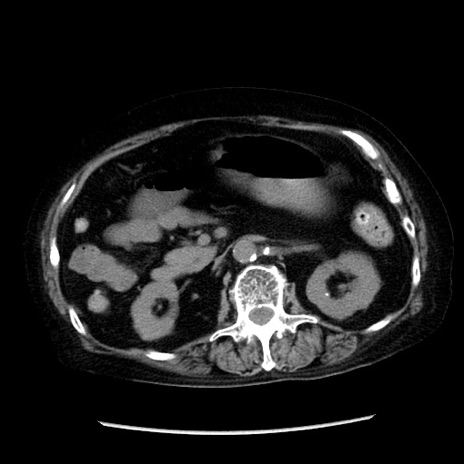

症例14(横断像)

【症例】 90歳代女性

【主訴】 腹痛・嘔吐

【現病歴】今朝から左側腹部痛を認めた。 経過観察していたが、嘔吐を認めたため来院。

【既往歴】 子宮癌術後

【身体所見】 意識清明、BP 127/54mmHg、P 98bpm Sp02 95%(RA)、BT 35.8°C、腹部平坦・軟腸ぜん動音聴取良好、右下腹部圧痛(+) 反跳痛なし

【データ】WBC 9800、CRP 0.46